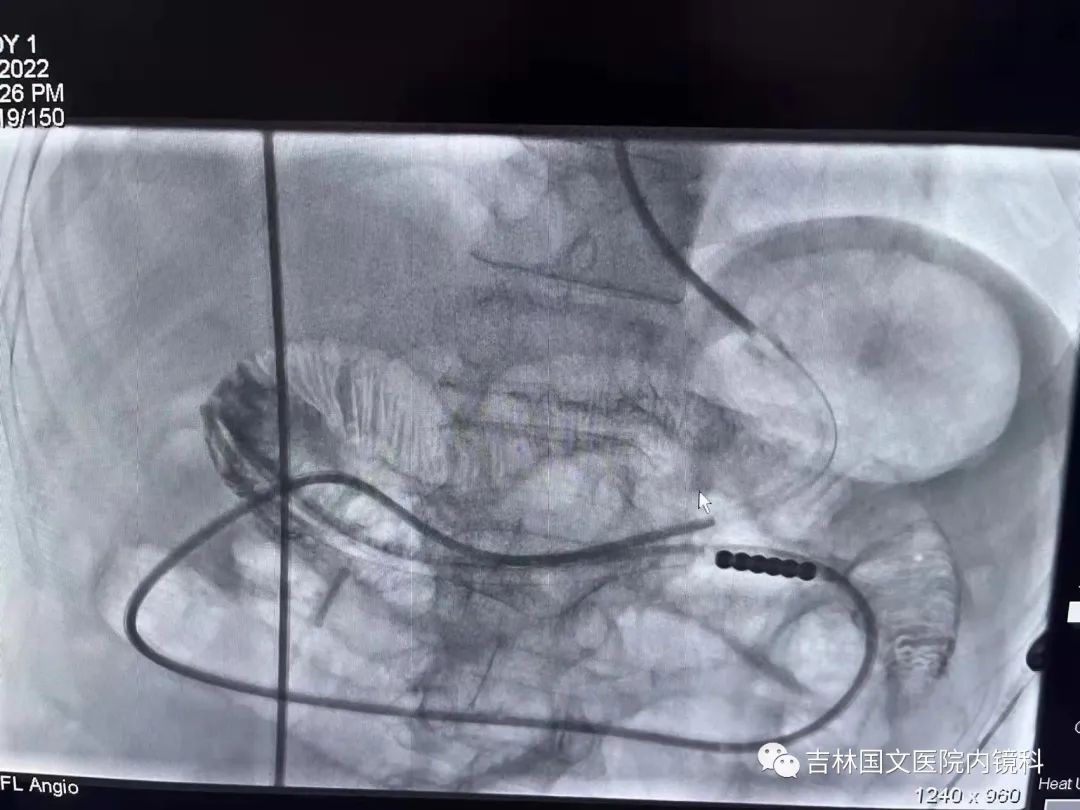

這是一位胃術(shù)后的患者,也就是說胃內(nèi)許多正常的解剖結(jié)構(gòu)都已經(jīng)切除,這就會造成腸梗阻導(dǎo)管易迷失方向,猜測哪邊才是真正的出口是這次操作成功的關(guān)鍵,這就需要我們的“第三只眼”--胃鏡,胃鏡再加上邢主任豐富的經(jīng)驗(yàn),在一個又一個岔路口為腸梗阻導(dǎo)管引路,判斷方向,遇山開荒,遇水搭橋,即使崎嶇,只要不放棄,終將成功。